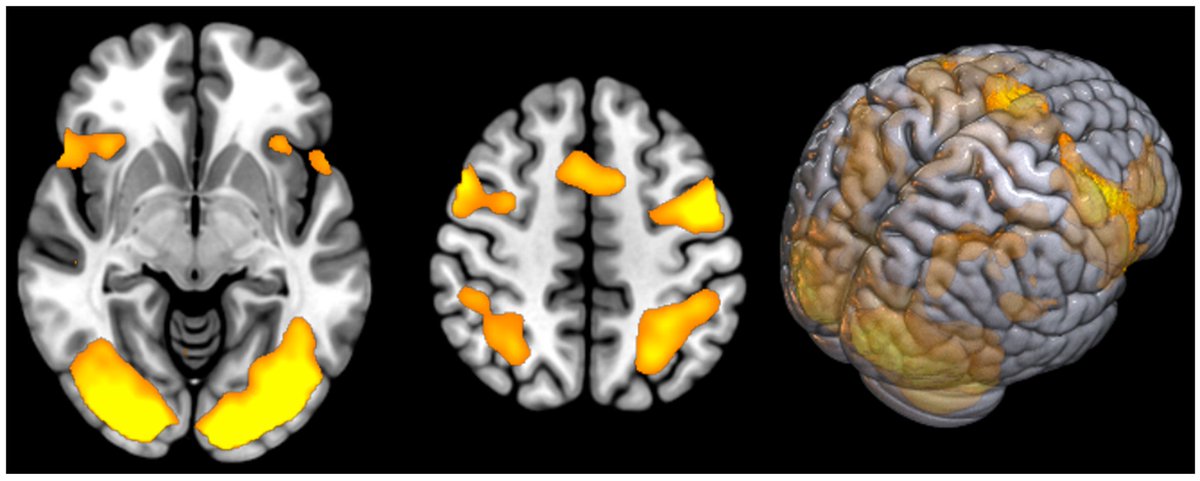

POST-COVID FATIGUE showed INCREASED ACTIVITY in BRAIN REGIONS involved in processing information, perceiving fatigue, and controlling movement

mdpi.com/2075-4418/14/1…Image

2) This study used a brain imaging technique called functional MRI to investigate the neurological basis of persistent fatigue and cognitive issues in people who have recovered from COVID-19. The researchers compared brain activity patterns in 30 patients ... Image

3) ...with post-COVID fatigue syndrome to 20 healthy individuals.

The key findings were that the COVID-19 patients showed significantly higher levels of brain activation in certain regions compared to the healthy controls. Image